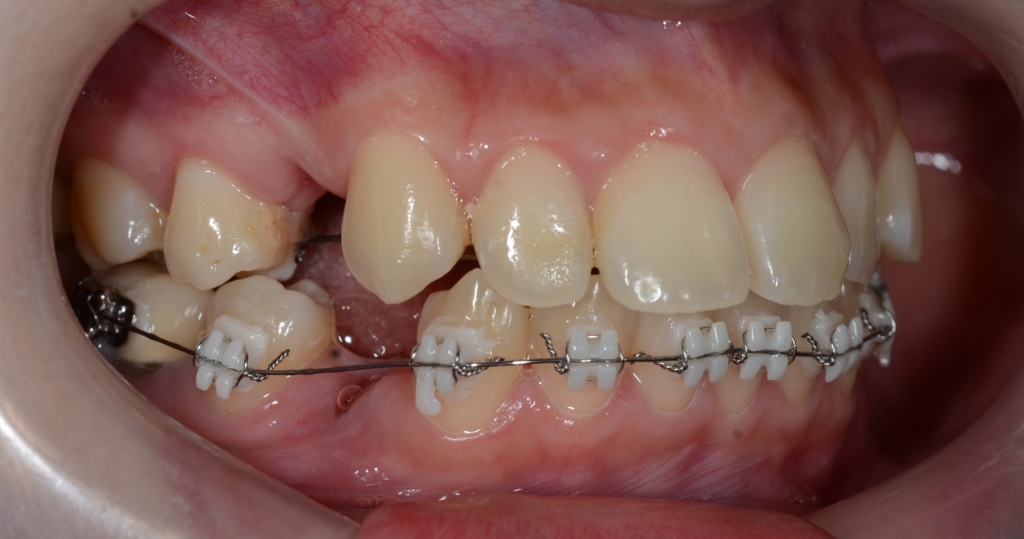

ついでに、歯並びの比較です

上段が矯正治療前、下段が矯正治療後